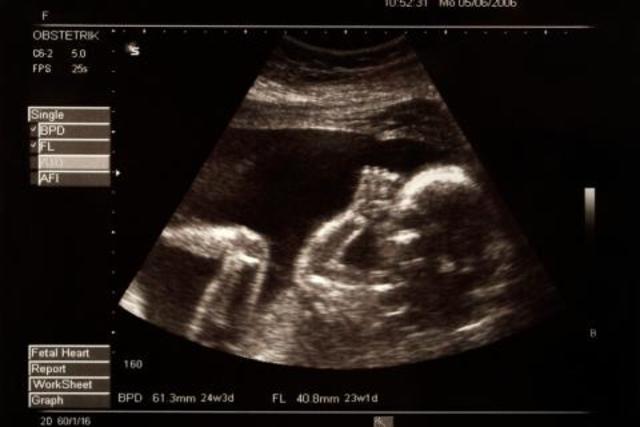

• Semana 24

Semana 24

Las cejas y las pestañas están bien formadas

Todas las partes del ojo están desarrolladas

El feto presenta el reflejo prensil y de sobresalto

Se comienzan a formar las huellas de la piel plantar y de la piel palmar

Se forman los alvéolos pulmonares

• Semanas 25 a 28

Semanas 25 a 28

Desarrollo rápido del cerebro

El sistema nervioso está lo suficientemente desarrollado para controlar algunas funciones corporales

Los párpados se abren y se cierran

El sistema respiratorio, aunque inmaduro, se ha desarrollado al punto de permitir el intercambio gaseoso